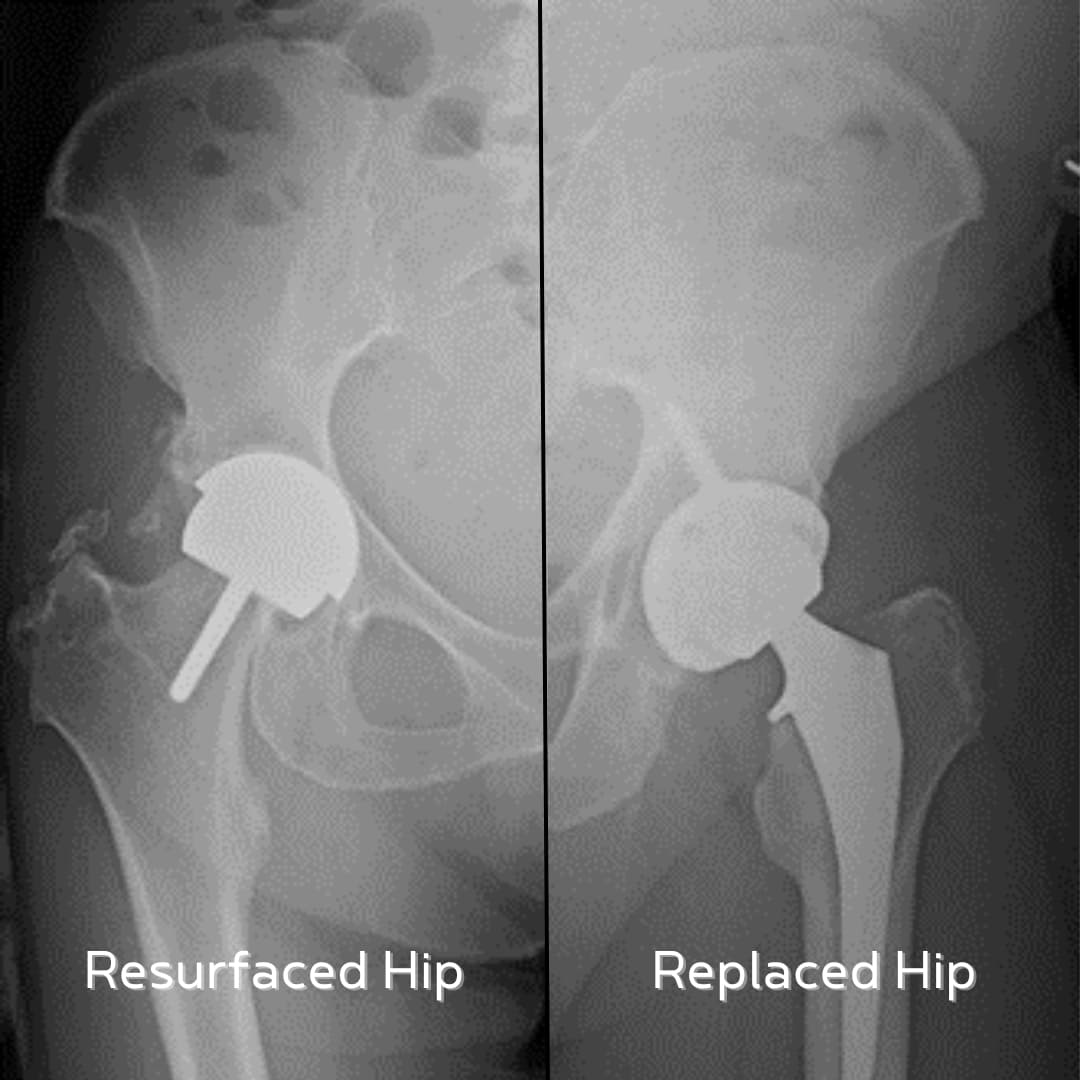

Hip resurfacing is a bone-preserving surgery. Instead of removing the entire femoral head (the ball of the hip joint), the surgeon trims it and caps it with a smooth metal covering. A metal cup is then placed in the hip socket.

A total hip replacement removes both the damaged femoral head and the socket. They are replaced with artificial parts, often made of metal, ceramic, or high-grade plastic.